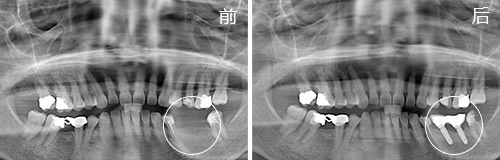

种植情况:种植2颗

种牙时间:2014年11月(已种牙1年9个月)